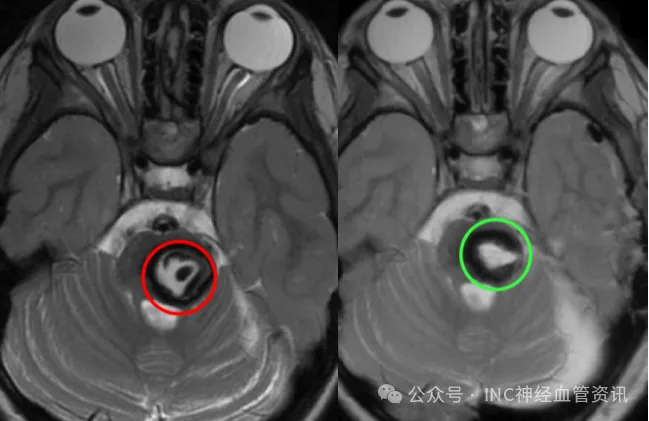

医生告知,从影像上看孩子可能已经历过数次脑干出血,虽未造成严重神经功能损伤,但随时可能再次出血威胁生命。由于脑干手术难度极大,当地医院建议保守观察。

术后复查MR显示病变全切,无脑水肿、出血等情况,无任何神经功能损伤。除了头发下一个小小的伤口,几乎看不出西西刚刚经历了一场开颅手术。